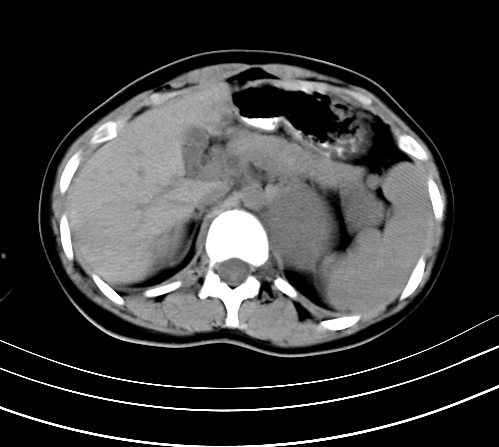

静脉期